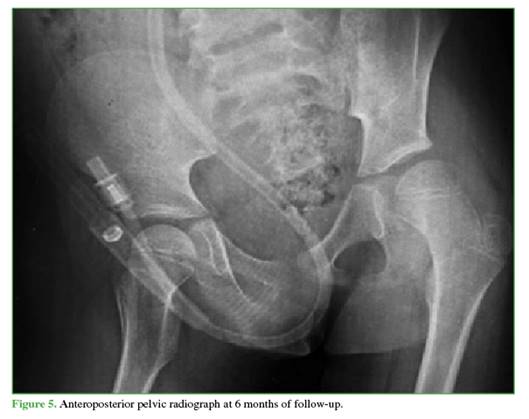

Follow-up radiographs at 3 (Figure 4) and 6 months (Figure 5) showed no evidence of AVN, and other musculo-skeletal complications associated with traumatic dislocation were also ruled out.

Reported complications include coxa magna, sciatic nerve palsy, paresthesias, and AVN of the femoral head.10 In patients under 18 years of age, the incidence after isolated dislocation ranges from 3% to 15%,17 and is higher if reduction is delayed.18 Therefore, imaging follow-up is essential. Although there is no consensus on ideal timing, in this case, check-ups were performed at 3 and 6 months, and no radiographic evidence of AVN was detected.

Follow-up radiographs showed no signs suggestive of AVN (sclerosis, collapse, cysts, joint-space narrowing, etc.).22 These findings may take 2 to 6 months to become visible on radiographs,20 so the follow-up schedule was appropriate.

Despite the absence of radiological signs of AVN up to 6 months, continued imaging follow-up is necessary to detect potential development of AVN, which may take up to 2 years to manifest.25